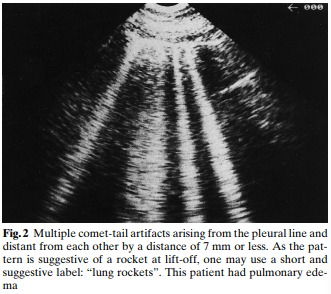

A significant portion of our current knowledge in lung ultrasound stems from Dr. Daniel Lichtenstein’s landmark paper in 1998. The paper discussed the use of artifacts to differentiate between pulmonary edema and COPD. Since that time some of the nomenclature was later redefined by Dr. Lichtenstein and what was then described as “roughly horizontal parallel reverberating lines” is now called A-lines and what was then called comet-tail artifact is now referred to as B-lines (defined as stretching below 16cm of depth). Additionally comet-tails artifact is now referred to as Z-lines and are defined distinct from B-lines and have no clinical significance:

“B” or B-lines can be seen in pneumonia, pulmonary edema, interstitial lung disease, atelectasis, and acute respiratory distress syndrome (ARDS).